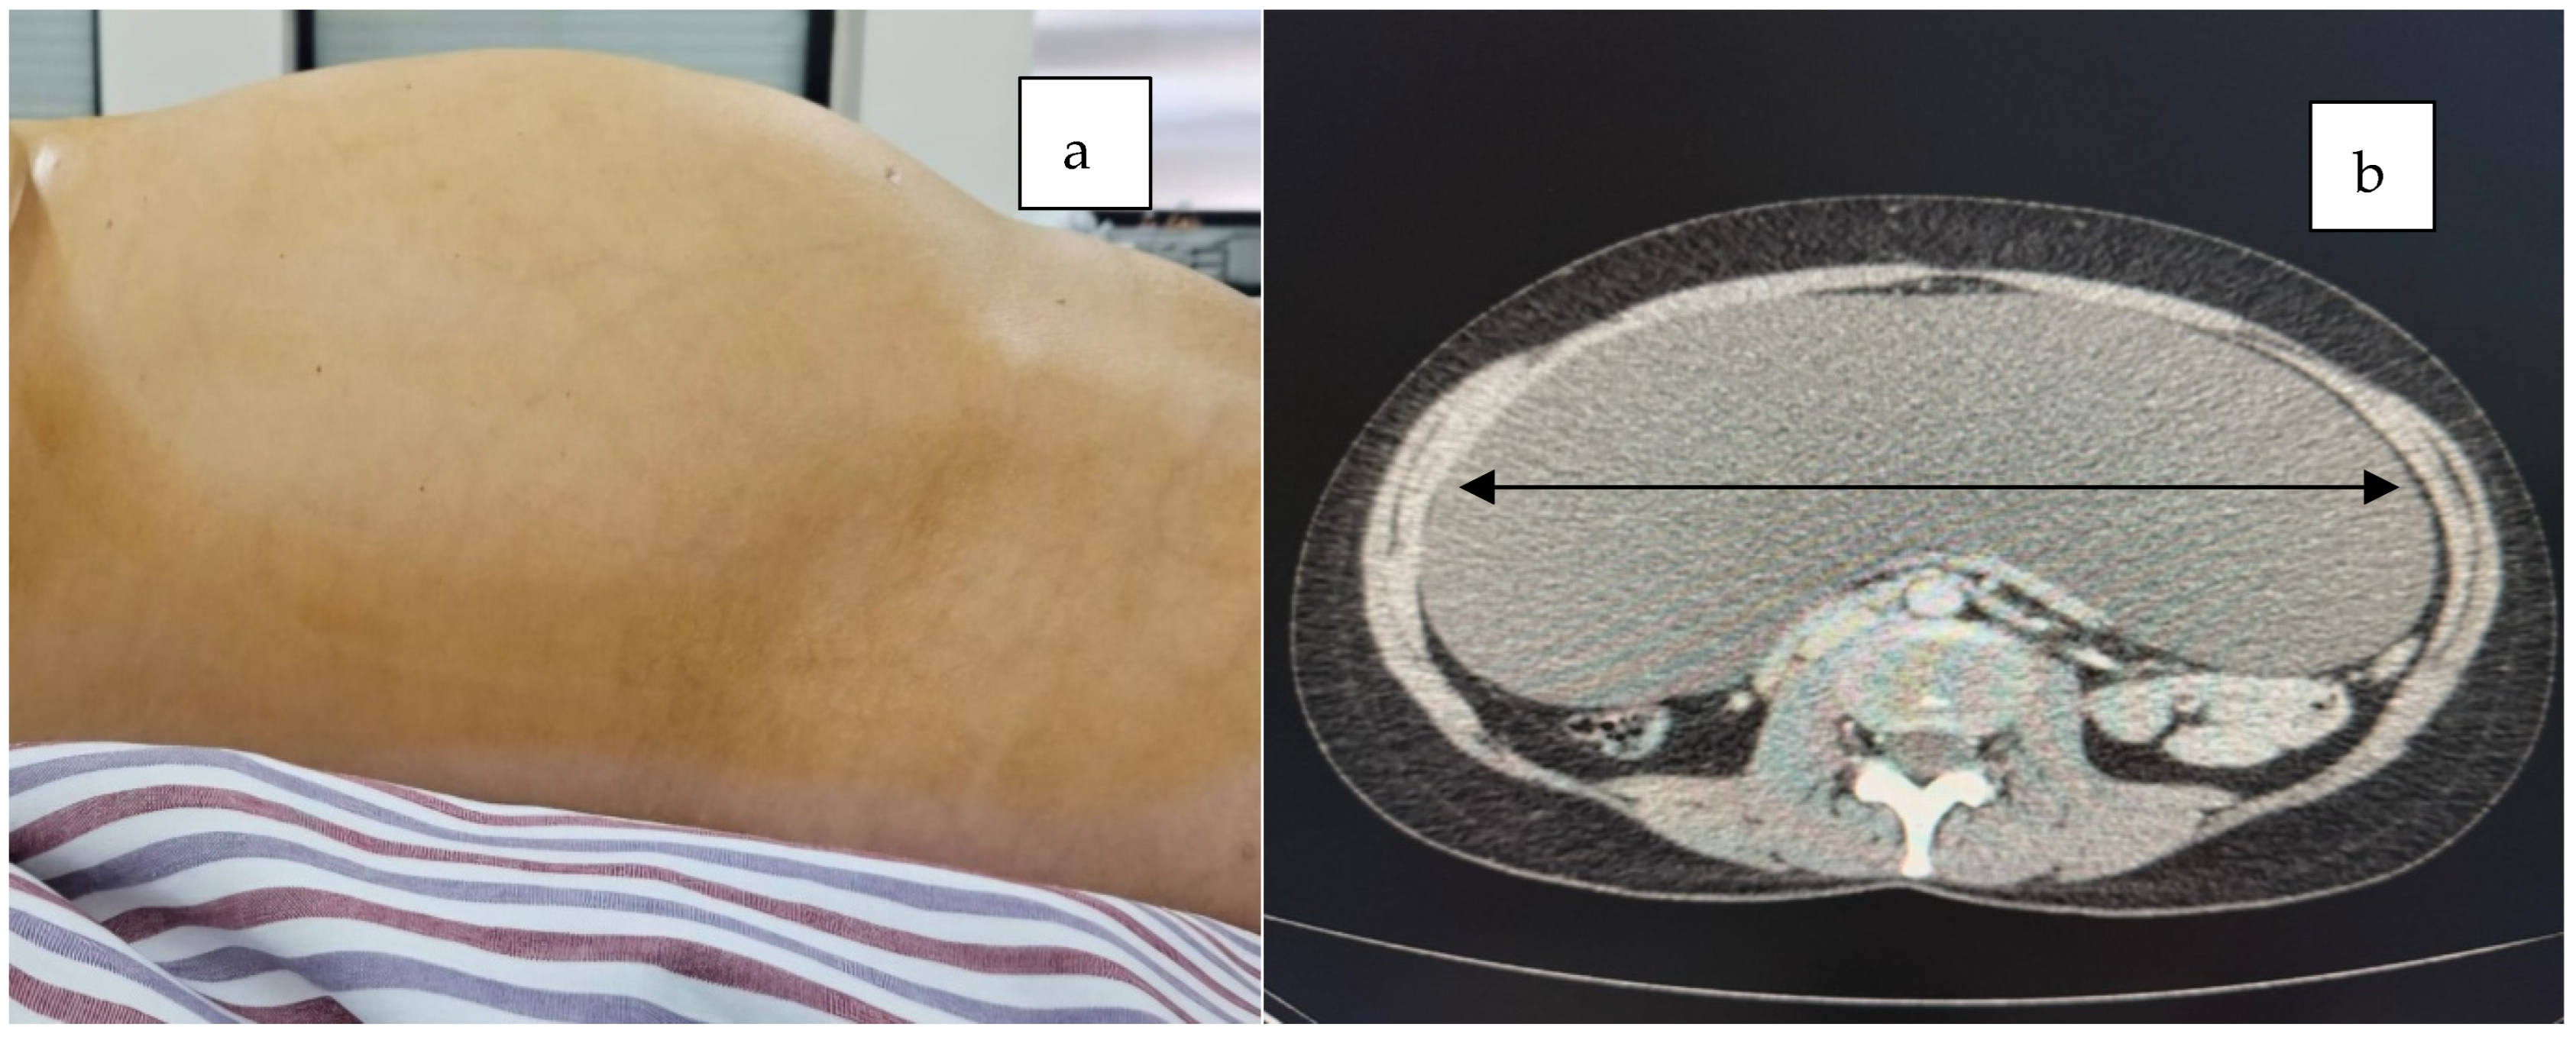

2. Case Presentation